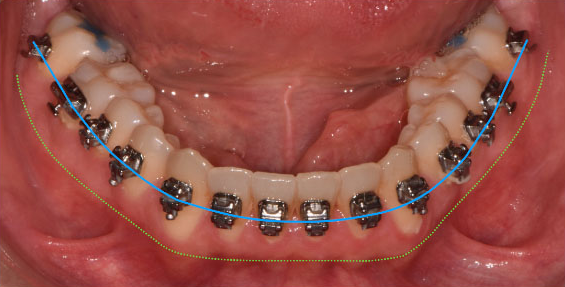

(Images: Intraoral Initial)

From the outset, bracket placement was the cornerstone of the treatment strategy. The upper central incisors were bonded 1–1.5 mm more gingivally than the canines, with laterals slightly lower, to recreate a natural curvature and protect the smile arc. Variable torque brackets were selected individually for each anterior tooth, according to its specific requirements. This feature of the Damon Ultima system represents a significant advantage: it combines the low-friction benefits of self-ligation with earlier expression of anterior torque. When paired with the rapid arch development characteristic of the system, this approach allows for the ideal torque to be achieved very early in treatment. As a result, proclination of the incisors is effectively avoided while maintaining efficient alignment.

The initial alignment was performed with light CuNiTi archwires, promoting gradual expansion and alignment while avoiding heavy forces. Progressively, the treatment advanced to the final 0.018 x 0.0275 stainless steel archwires, ensuring full torque expression and establishing control over the occlusal plane.